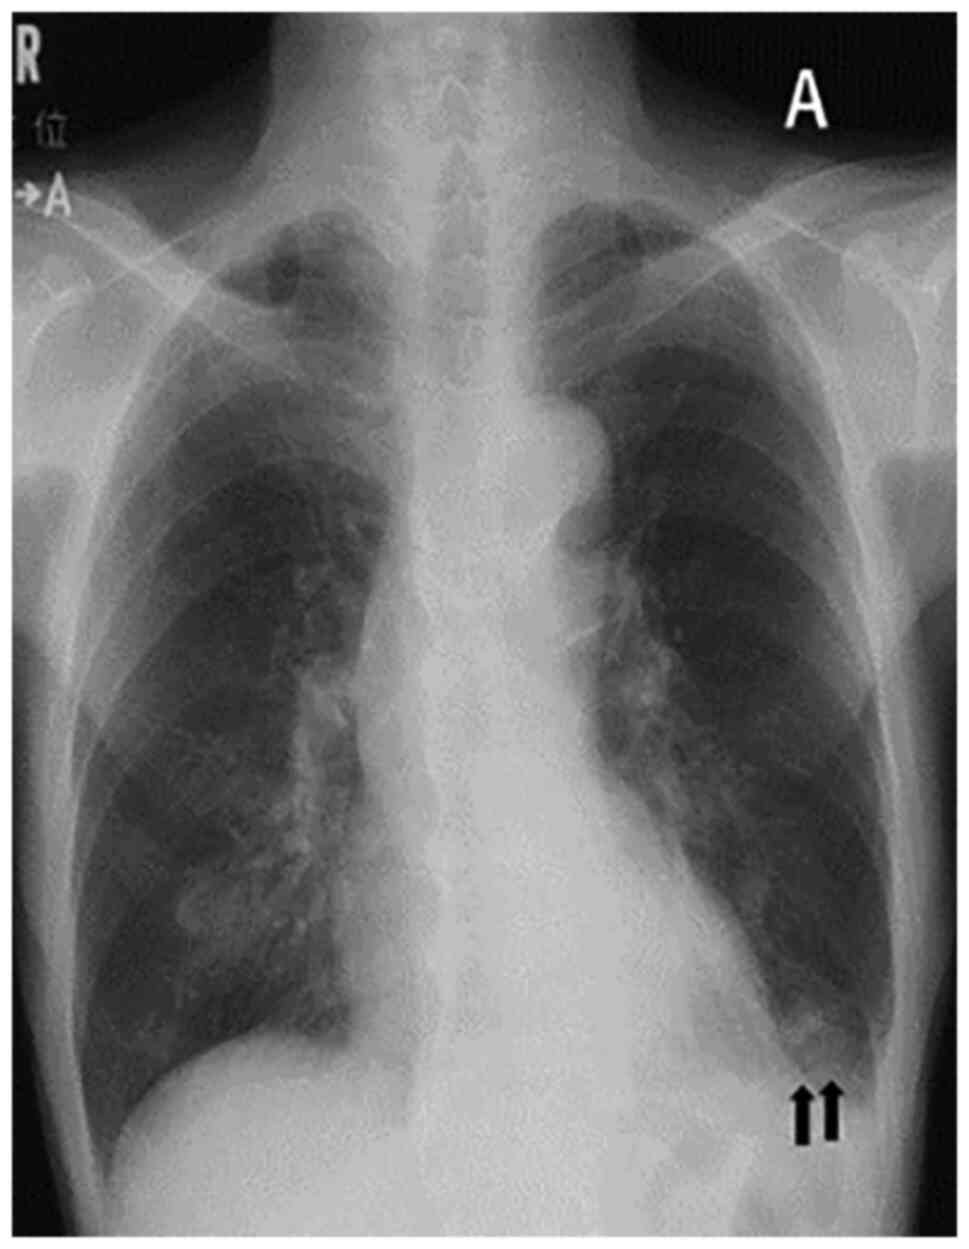

An 82-year-old man visited the Nagoya City University West Medical Center (Nagoya, Japan) in March 2017 with a chief complaint of epigastric pain that started 3 months earlier, and he was diagnosed with stage IV gastric cancer. Tegafur/gimeracil/oteracil (TS-1) was administered as first-line chemotherapy (40 mg twice/day, consisting of 42-day cycles of 28-day consecutive administration followed by 14-day drug holiday, for a total of 9 cycles), and paclitaxel was administered as the second-line chemotherapy (65 mg/m2 on days 1, 8 and 15 every 4 weeks for a total of 2 cycles), but neither treatment was effective. Due to increased bleeding from the tumor, the patient received radiation therapy (45 Gy) to control the bleeding. In October 2018, the patient was initiated on nivolumab (240 mg every 4 weeks) as the third-line chemotherapy; the nivolumab treatment induced a partial response, and was thus continued. After the 22nd course of the treatment, the patient experienced loss of appetite for 1 week, and was then referred to the Department of Respiratory Medicine of the Nagoya City University West Medical Center due to the appearance of infiltration shadows in the lower lobe of the left lung on chest X-ray (Fig. 1A) and chest CT (Fig. 2A) images. On the chest CT images taken 3 months ago, no abnormality was found bilaterally in the lung fields. The patient had no fever, and the blood test results revealed a white blood cell count of 5,200/µl (normal range, 3,300-8,600/µl) and a C-reactive protein level of 0.6 mg/dl (normal range, 0.0-0.3 mg/dl). The patient received moxifloxacin per os 400 mg/day for 7 days on suspicion of bacterial pneumonia, but no treatment was administered subsequently as his condition and inflammatory response on blood tests were stable. One month later, the CT findings revealed an exacerbation, the infiltrative shadow in the lower left lobe had expanded, and other inflammatory shadows appeared in the left lingula and the lower lobe of the right lung (Fig. 2B); however, no fever or oxygen desaturation were observed. The results of the blood examination that was performed at that time are listed in Table I. No obvious abnormalities were observed, except for a slight increase in the C-reactive protein level to 3.2 mg/dl. Mycobacterium intracellulare was detected twice in sputum cultures performed at the time, and no other causative bacteria were detected. The shadows were found mainly in the lower lobe of the left lung, and not in the middle lobe, lingula or lung apex, where lesions are usual observed in MAC-LD, so treatment for bacterial pneumonia was again administered. Meropenem at a dose of 1,000 mg/day was selected as an antibiotic and the nivolumab treatment was discontinued; however, the lung shadows were further exacerbated after 4 weeks (Fig. 2C) and the case was diagnosed as MAC-LD. The standard treatment for MAC-LD is clarithromycin 500 mg twice per day, rifampicin 10 mg/kg per day and ethambutol 15 mg/kg per day (12). Since the patient weighed 45 kg, the standard doses for rifampicin and ethambutol were 450 and 675 mg/day, respectively. However, as the patient was at an advanced age and suffered from gastric cancer, a decision was made to start with a dose lower than the standard dose of each drug, and treatment with all three drugs was initiated: Clarithromycin 600 mg/day, rifampicin 300 mg/day and ethambutol 500 mg/day. Since it became difficult to continue treatment due to severe nausea as a side effect of the treatment, the medication schedule was changed from daily to 3 times per week, after which time the nausea markedly improved and the patient was able to continue receiving treatment. At 3 months after the start of medication, the lung shadows improved (Fig. 2D), and at 7 months after the start of treatment the sputum cultures became negative for acid-fast bacilli. Although resumption of nivolumab was considered, the patient declined treatment. He is currently being followed up and is on vonoprazan fumarate (20 mg/day), but receives no chemotherapy for gastric cancer. An abdominal CT examination in August 2021 revealed thickening of the gastric wall, raising the suspicion of disease recurrence. The date of the last follow-up visit was 19 October 2021, at which time no infiltrative shadow in the lung was detected.

Figure 1

Chest X-ray showing infiltration shadows in the left lower lung field (arrows) (A).